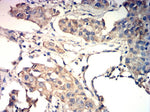

Sku: OM641860